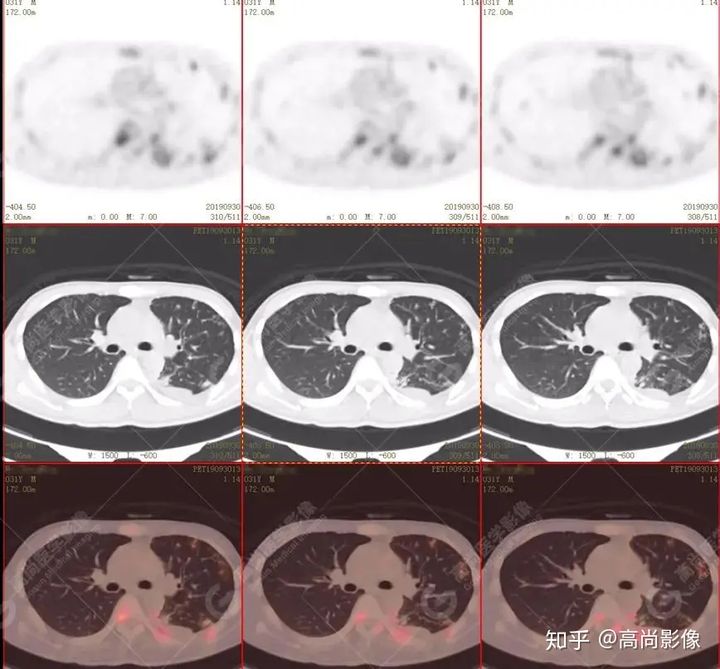

左肺上葉尖后段及下葉背段多發(fā)簇狀斑點(diǎn)狀高代謝灶

左側(cè)胸膜結(jié)節(jié)樣增厚,代謝不同程度增高

【PET/CT提示】雙肺、左側(cè)胸膜多發(fā)結(jié)節(jié)影,全身多處骨質(zhì)破壞,全身多發(fā)淋巴結(jié)腫大,代謝攝取不均勻性增高。